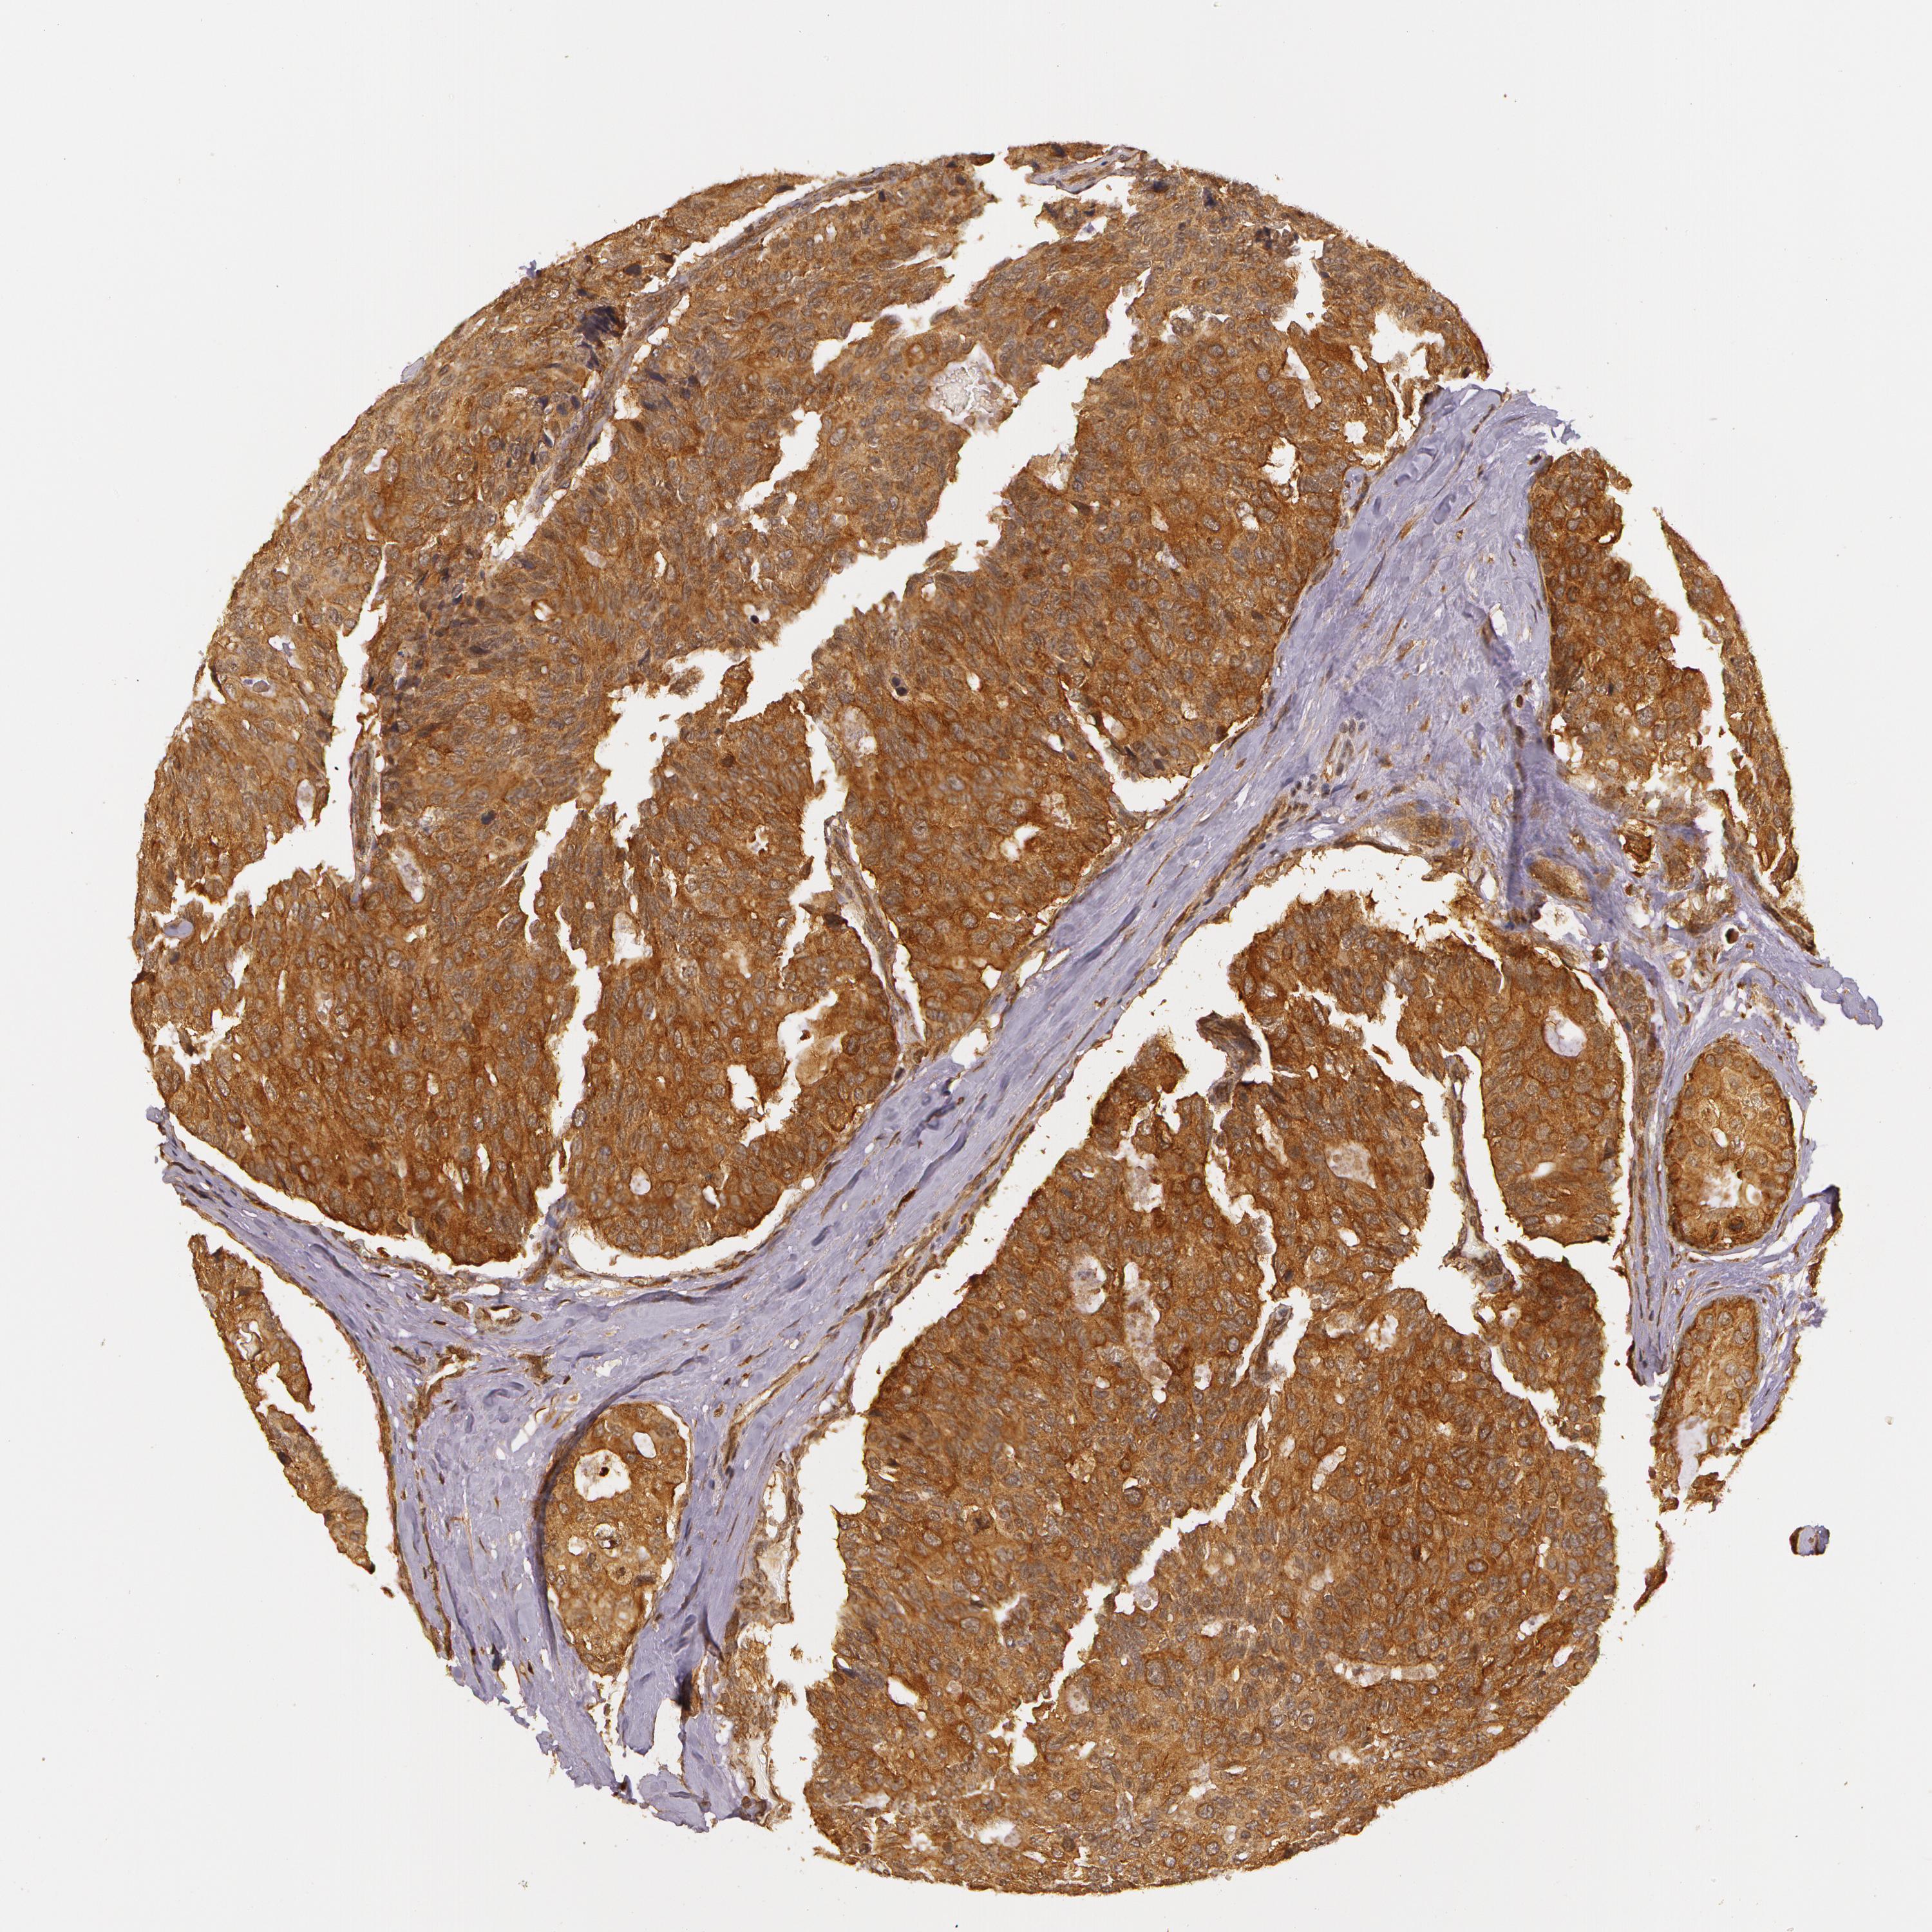

CANCER BREAST CANCER Show tissue menu

BRCA TCGA BRCA VALIDATION PROTEIN EXPRESSION